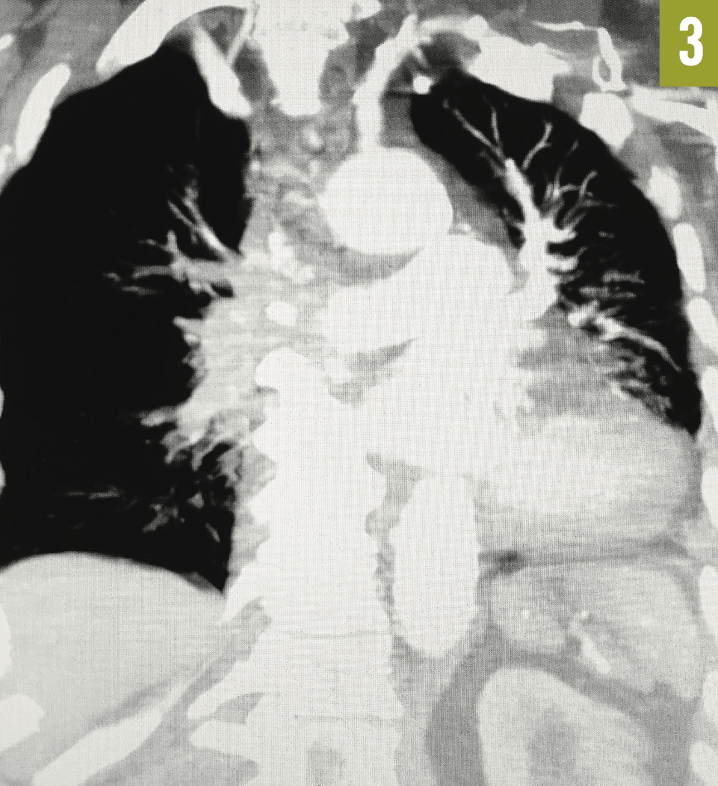

Venous duplex ultrasonography of the left leg confirmed the presence of deep-vein thrombosis. Computed tomography angiography (CTA) of the chest showed a large embolus in the right main pulmonary artery, almost completely occluding the lumen of the vessel (Figure 1). A few peripheral emboli were present in the left lung, as well. Perfusion to the entire right lung was markedly diminished, and there was a compensatory increase in the perfusion of the left lung (Figures 2 and 3). The radiographic findings were consistent with the Westermark sign.

Figure 3: Coronal CTA of the chest showed markedly reduced vascularity of the right lung and compensatory hypervascularity of the left lung.